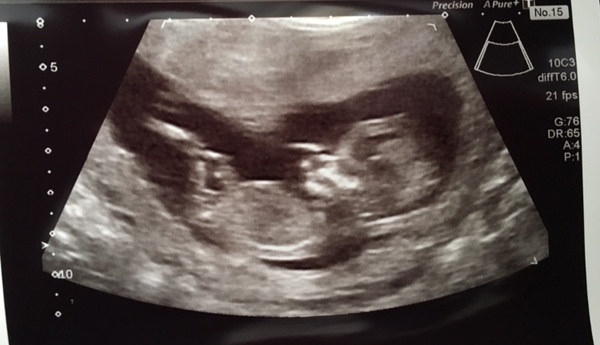

@Villagefete here’s my 12 week (although actually 13 weeks) scan. I haven’t a clue what you look for but I was told the nub was girly.

Sorry @villagefete I forgot the picture πŸ€¦β€β™€οΈ

I swear I’m forgetting everything at the moment. I left the house unlocked with the key in the door yesterday.

@MisBit1 Awwww. I'm rubbish at nub theory, but such a sweet scan, congrats. :)

@MisBit1 Very cute scan!